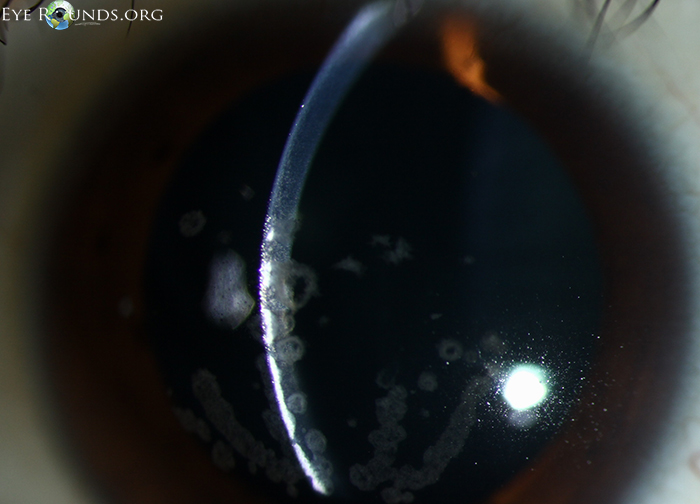

각막의 기질에 빵부스러기, breadcrumb 모양의 흰색의 침착물이 쌓이는데,

이는 각막의 중심부, 기질의 앞쪽쯕에 모이게됩니다.

혼탁의 모양은 둥글며, 병변들의 윤곽이 명확하며

흔히 눈송이, 빵부스러기 등의 모양으로 하고 있으며, 경계가 명확하여,

병변이 없는 부위과 구분됩니다.